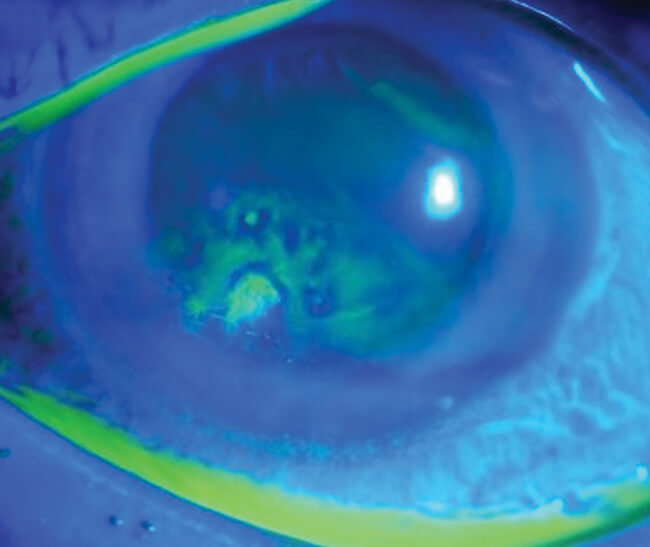

Figure 2: Fluorescein staining showing abnormal uptake suggestive of recurrent corneal erosion [16].